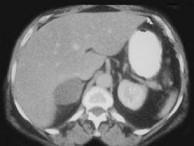

问题 女,45岁,满月脸、向心性肥胖2年余,实验室检查:血、尿皮质醇增高,请结合CT图像,作出诊断()

选项 A.左肾上腺腺瘤 B.左肾上腺腺癌 C.左肾上腺转移瘤 D.左肾上腺嗜铬细胞瘤 E.左肾上腺增生

答案 A